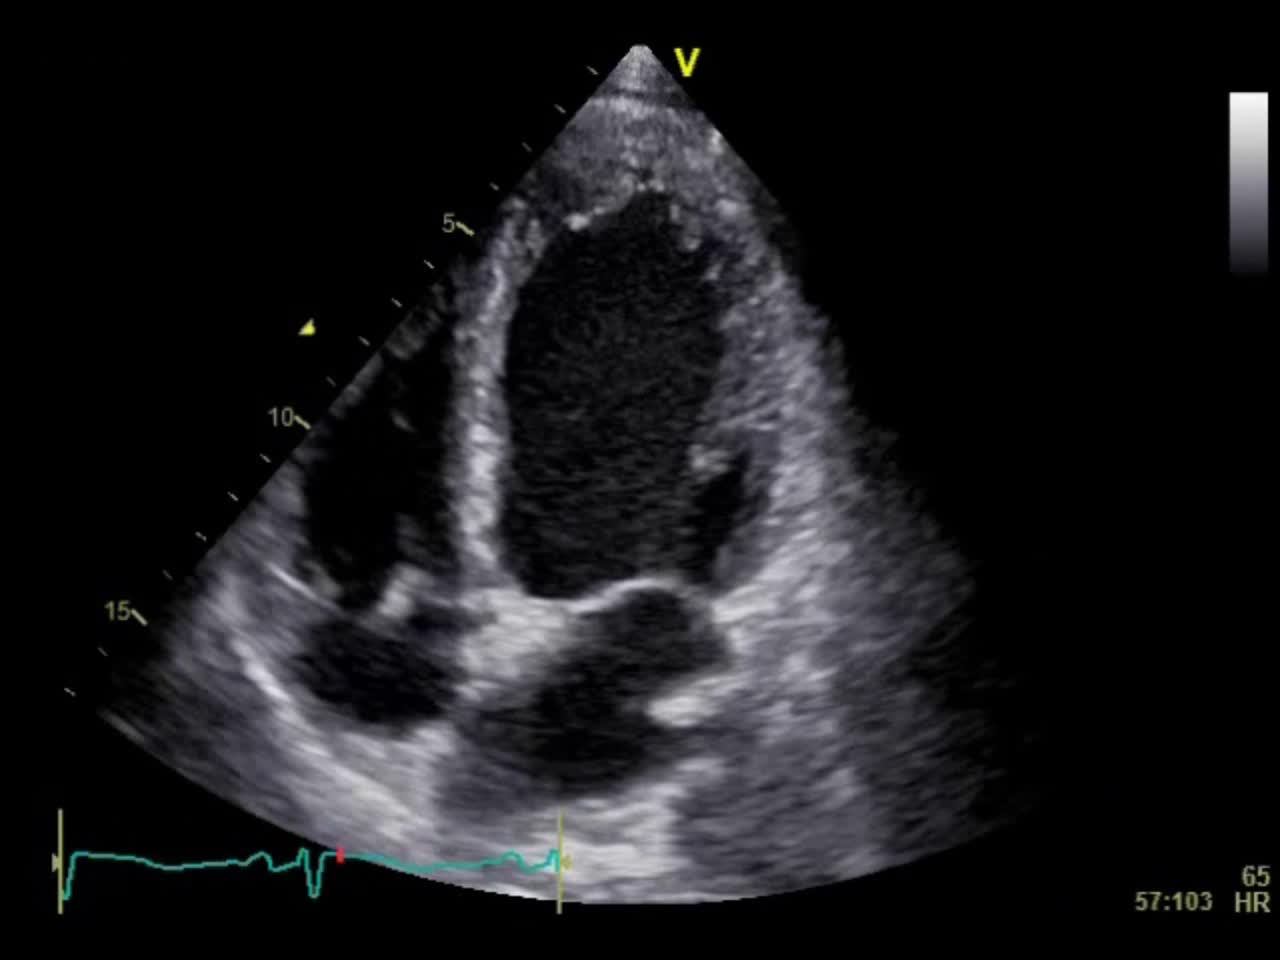

動画21-2 心エコー②(心尖部四腔像)...

00:00:05